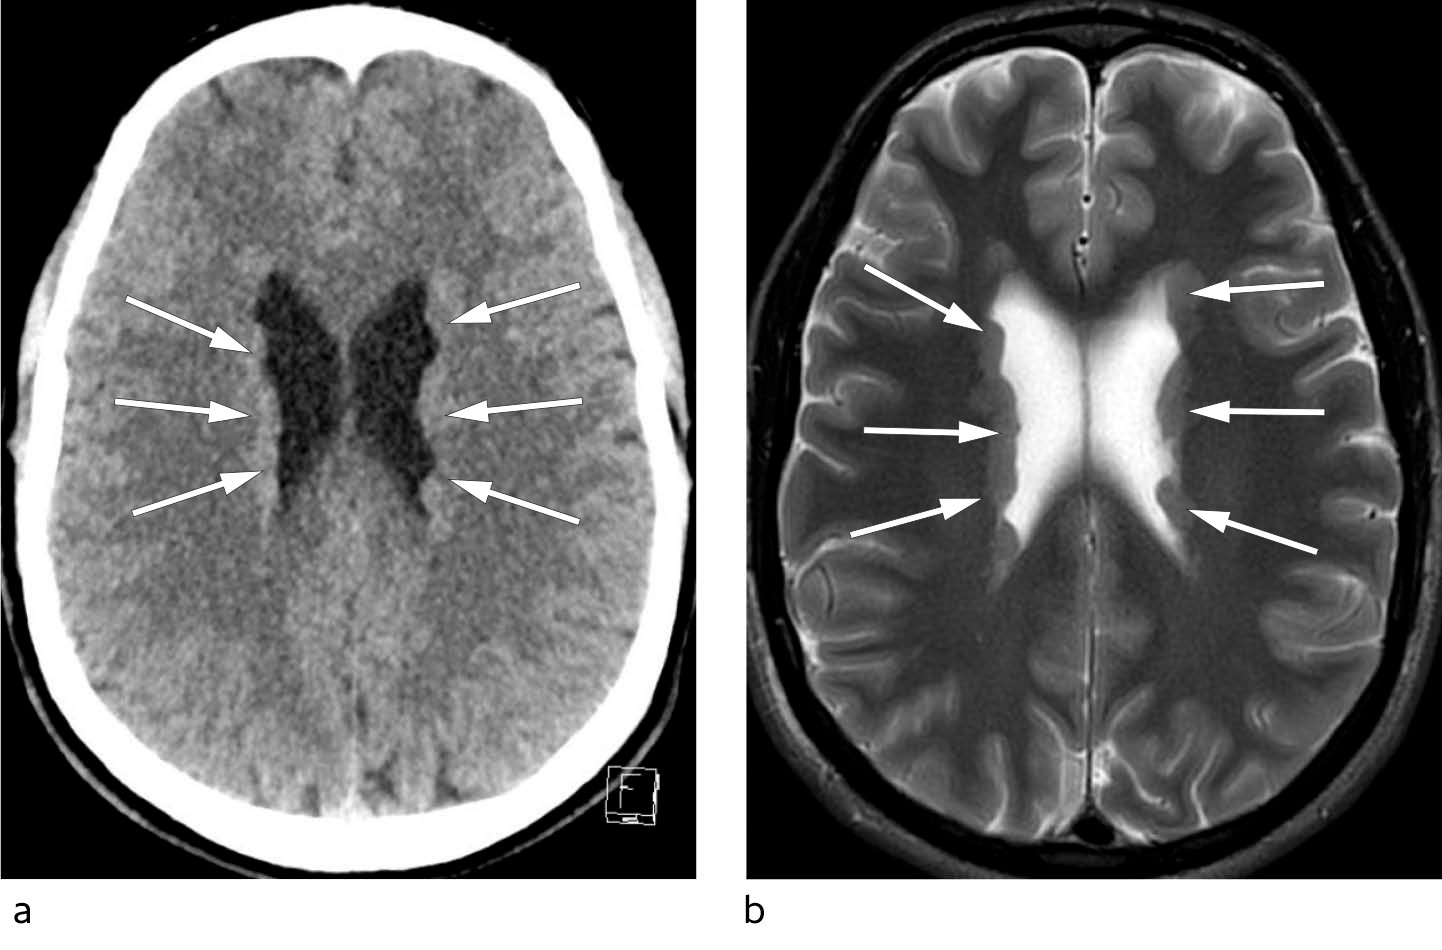

I den videre utredningen ble det beskrevet normale funn ved interiktalt EEG. Langtids-EKG avdekket vekslende atrioventrikulære (AV) blokkeringer med bradykardiepisoder (AV-blokk grad 2, type II (Mobitz' type)) (figur 2). På bakgrunn av anamnese og EKG-funn ble det konkludert med at pasienten mest sannsynlig hadde hatt en kardial synkope forårsaket av AV-blokk grad 2, type II. Denne hjerterytmeforstyrrelsen har en klasse I-indikasjon for pacemaker (1), og pasienten fikk implantert en tokammerpacemaker før han ble utskrevet i god form.

I sin kasuistikk presenterer Ihle-Hansen et.al en lite kjent årsak til kortvarig bevissthetstap. Pasienten hadde initialt fått implantert en tokammerpacemaker på grunnlag av AV-blokk grad 2, type II (Mobitz). EKG-registreringen i figur 2 viser imidlertid AV-blokk grad 2, type I (Wenckebach) med gradvis økende PQ-tid før bortfall av AV-overledningen og kortere PQ-tid på første kompleks etterpå. AV-blokk grad 2, type I (Wenckebach) er ikke unormalt hos friske 20-åringer og gir vanligvis ikke indikasjon til implantasjon av pacemaker. Det i kasuistikken beskrevne videre pasientforløp med nytt bevissthetstap og funn av ikke-kardial årsak (periventrikulær nodulær heterotopi) gir retrospektivt ytterligere støtte for mistanken om ikke indisert pacemakerimplantasjon.

Ihle-Hansen og medarbeidere beskriver en ung mann som hadde hatt et bevissthetstap og fikk påvist epilepsi pga. strukturelle forandringer i hjernen (1). Til tross for funn ved cerebral CT og epilepsisuspekt klinikk, implanterte man pacemaker. Grunnlaget var at EKG-monitorering skal ha vist AV-blokk grad 2 type 2, hvilket forfatterne hevder er en kl. I-indikasjon for pacemaker.

Den korte EKG-stripen som er publisert viser at én enkelt P ikke følges av QRS. Første PQ-tid etter er kortere enn de foregående. Med et så kort utsnitt skal jeg ikke være skråsikker. Men man må mistenke at «blokket» ikke var type 2, men type 1 (Wenckebach). Om det er variasjoner i PQ-tid ellers i registreringen, før eller etter den P som mangler QRS, taler dette for blokk med mekanisme av type 1. Likeledes om det er oppbremsing av sinusaktiviteten samtidig. Slike funn skyldes som regel vaguspåvirkning, ikke sykdom i ledningssystemet. Det er dessuten den langt vanligste årsaken til «AV-blokk» hos en ung person. Slike «blokk» skal ikke behandles (2). Om man legger til grunn at «blokket» var type 2, er det heller ikke indikasjon, dersom årsaken bør antas å være vagal påvirkning (2). Når forfatterne hevder det påviste «blokket» er kl. I-indikasjon for pacemaker, tolker de etter min oppfatning retningslinjen feil. Pacemakerindikasjon forutsetter antatt eller påvist sykdom i ledningssystemet. I så fall skal det utredes, før man gir pacemaker, når pasienten er ung (4).